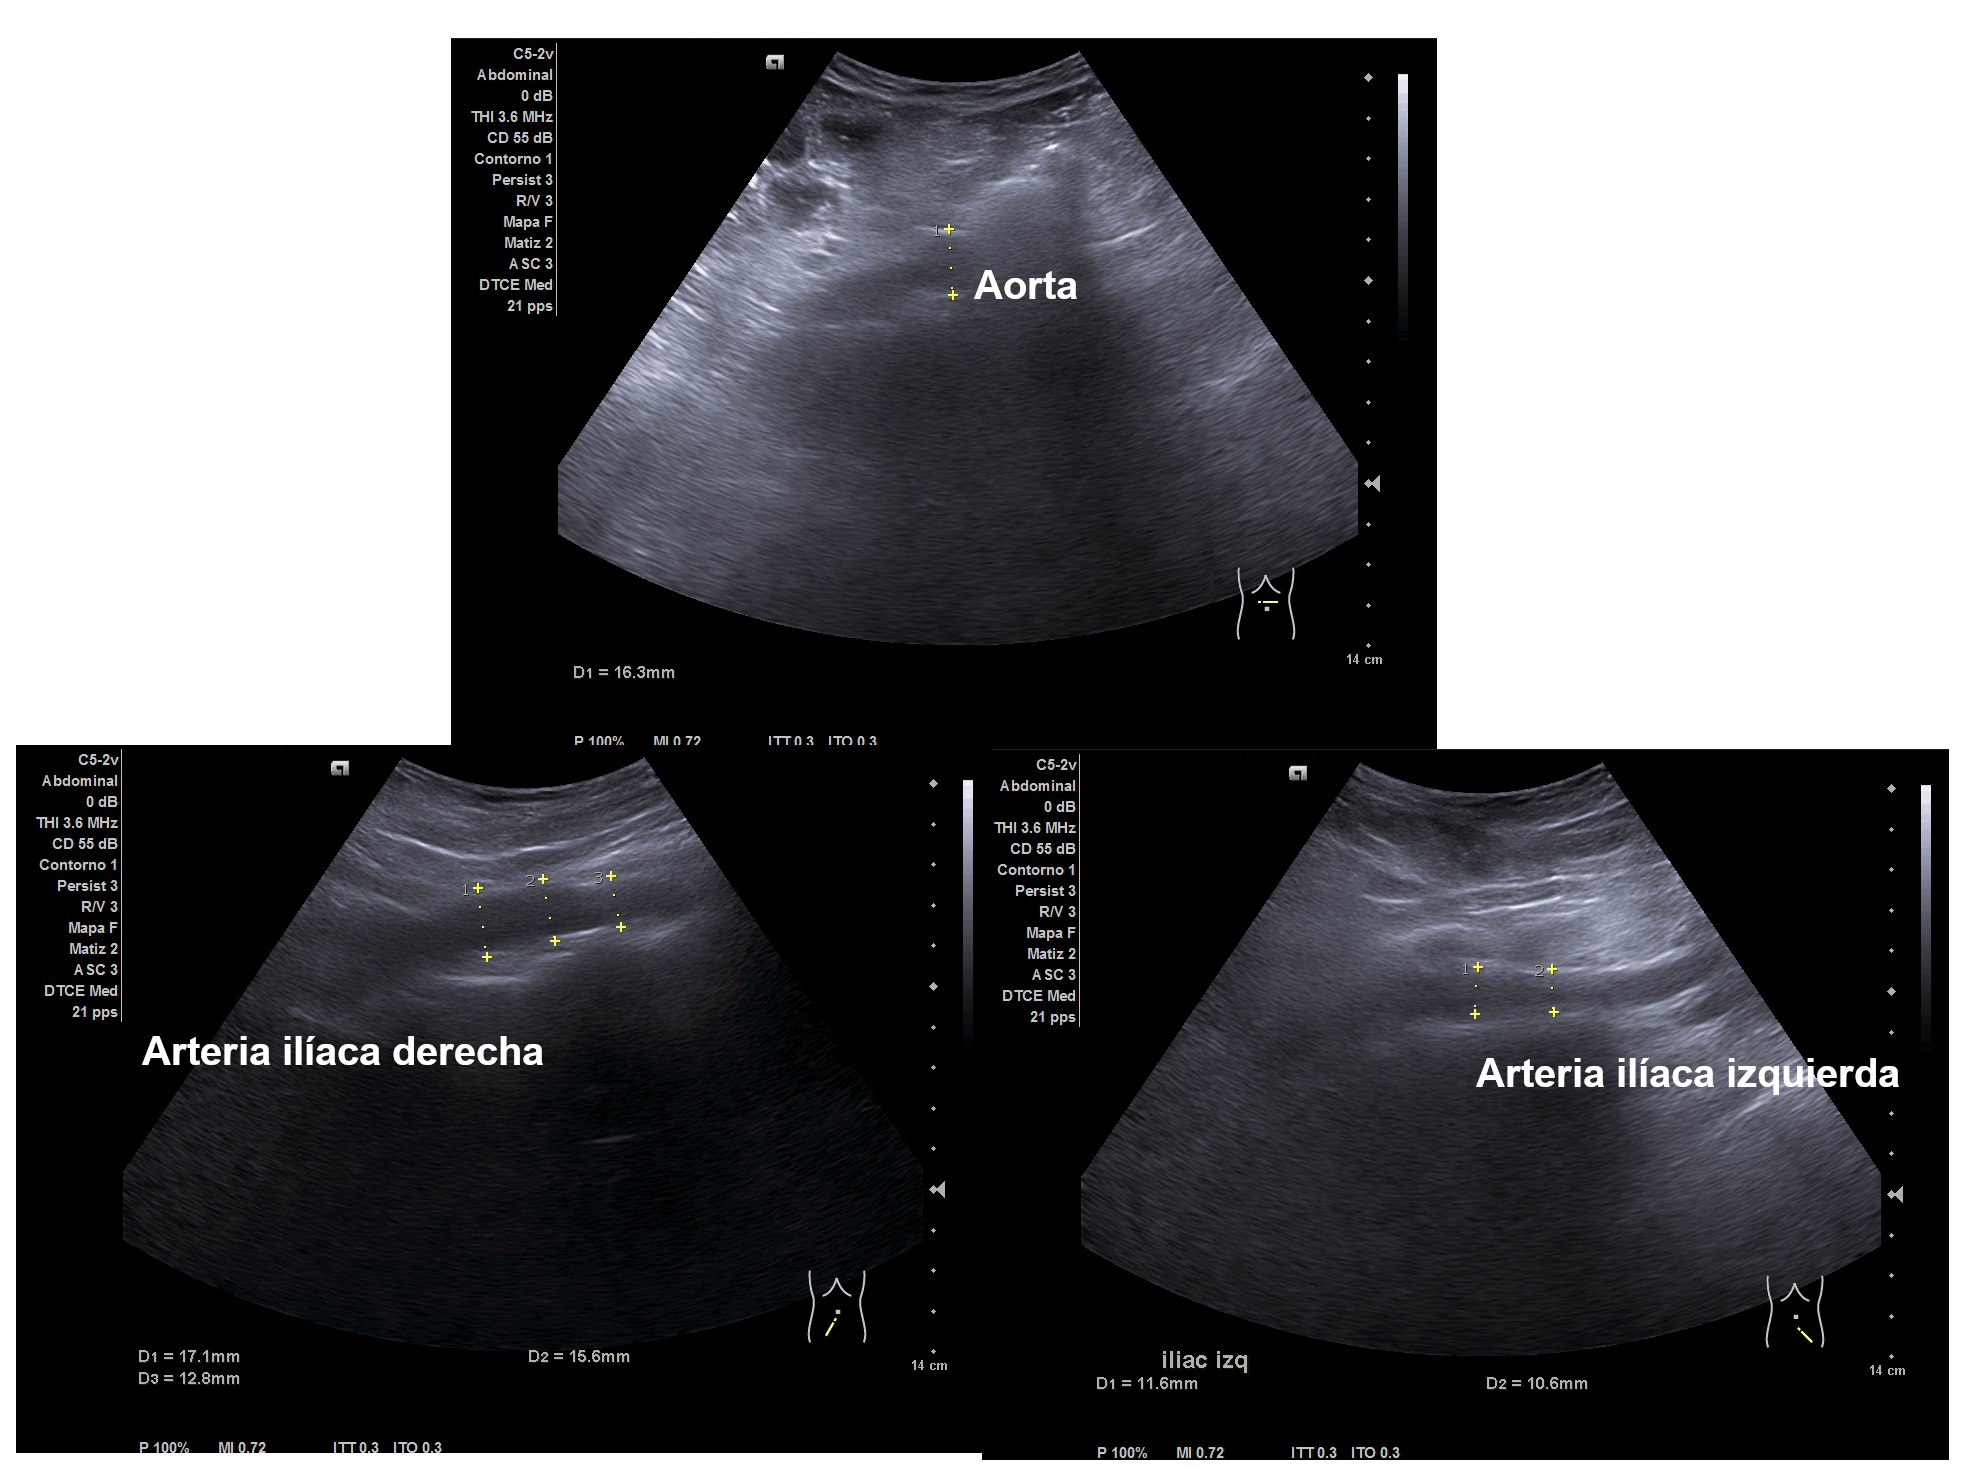

Parenquima hepatico sin alteraciones, vesícula biliar sin imagenes hiperecoénicas en interior. Pancreas visible en parte, sin alteraciones. Asimetría entre ambos riñones compatible variante de la normalidad RI. Llama la atención dilatación ilíaca derecha al comparar con contralateral y con aorta abdominal distal. Compatible con dilatación aneurismática ilíaca derecha.

Abdominalgia en estudio + Dilatación aneurismática ilíaca derecha.

El diagnóstico diferencial del Aneurisma Ilíaca con: Displasia fibromuscular u otra patología del tejido conectivo, lúes o tuberculosis entre otros. Toda dilatación que sobrepase el 50% del diámetro del vaso se considera aneurismática. Por la edad no se plantea el origen ateromatoso.

La ecografía en Atención Primaria se plantea en el contexto de responder a una pregunta clínica tras la anamnesis y la exploración física u otras pruebas complementarias que se precisen. A resaltar, la importancia de realizar ecografía completa siguiendo una sistemática y prestando atención tanto a variantes de la normalidad como a hallazgos patológicos. En el caso de la ecografía abdominal, es fundamental explorar los grandes vasos tanto en plano transversal como longitudinal, haciendo incapié en la división de las ilíacas.